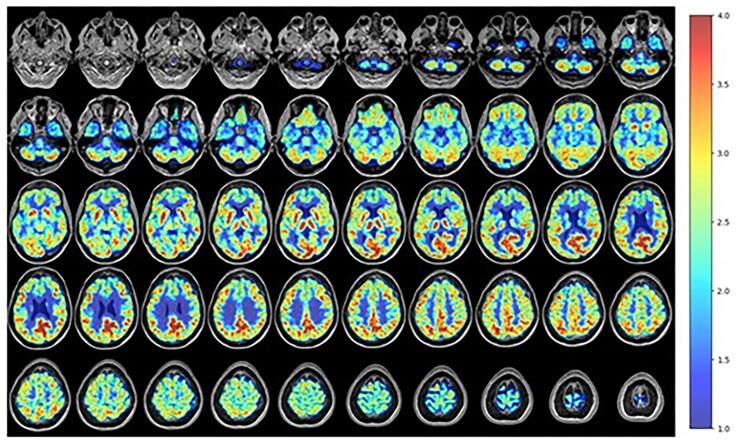

Case presentation: Our participant is a 58 year-old male with a past medical history notable for alcohol use disorder and BD (unspecified type) who underwent PET imaging with the mitochondrial complex I PET ligand 18F-BCPP-EF. The resulting images demonstrated significant overlap between areas of dysfunction identified with the 18F-BCPP-EF PET ligand and prior functional magnetic resonance imaging (MRI) techniques in the setting of BD. That overlap was seen in both affective and cognitive circuits, with mitochondrial dysfunction in the fronto-limbic, ventral affective, and dorsal cognitive circuits showing particularly significant differences.

Abstract Image